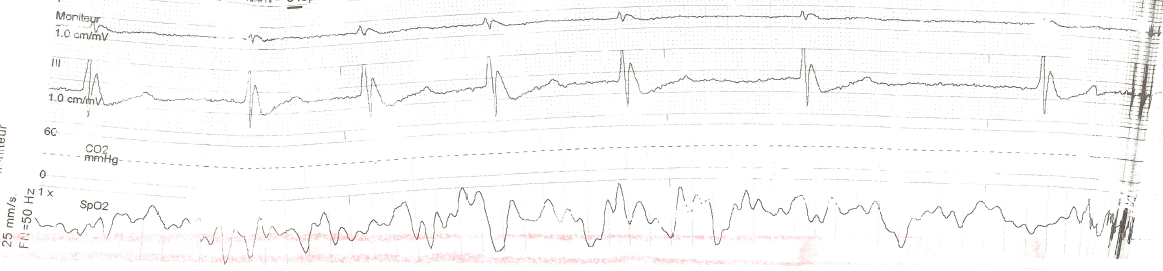

Cet ECG 3 dérivations est celui d’un patient en hypothermie accidentelle sévère en préhospitalier et montre une bardycardie et onde J’Osborn.

Le terme onde J désigne la formation d’une onde lorsqu’il existe une surélévation du point J par rapport à la ligne de base de plus de 1 mm, présente sur deux dérivations consécutives. Cette onde forme un crochetage de la branche terminale du QRS, avec surélévation en dôme.

En cas d’hypothermie, l’onde J est le plus souvent retrouvée II, III, aVF, V3-V6 sur un ECG 12 pistes. Son incidence varie dans l’hypothermie, de 50 à 80 % des cas, jusqu’à 100 % lors d’hypothermie sévère (< 28°) selon les séries. Son amplitude et sa présence seraient inversement proportionnelles à la profondeur de l’hypothermie mais influencées également par d’autres facteurs (l’acidose par exemple).